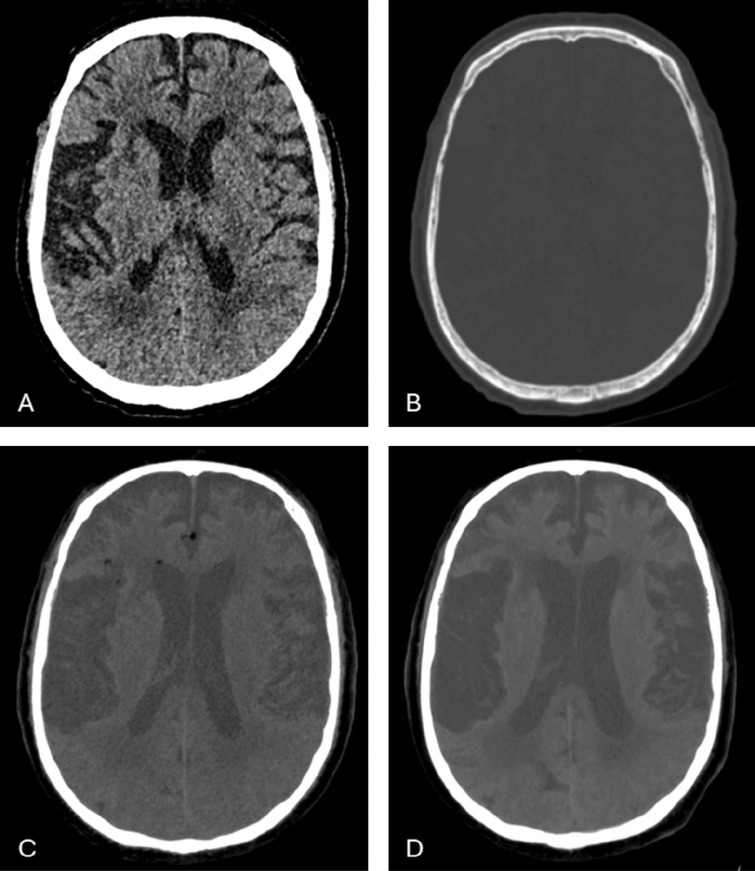

A 73-year-old patient with a complex sacral fracture underwent stabilising orthopaedic surgery. Postoperative brain CT showed fat droplets in the subarachnoid space and lateral ventricle. These fat droplets migrated into the cerebrospinal fluid by a tear in the sacral thecal sac. Teaching point: Intracranial subarachnoid fat droplets may be observed after spinal surgery.

一位73岁的复杂骶骨骨折患者接受了稳定骨科手术。术后脑CT显示蛛网膜下腔及侧脑室有脂肪滴。这些脂肪滴通过骶鞘囊的裂口迁移到脑脊液中。教学点:脊柱术后可观察到颅内蛛网膜下腔脂肪滴。